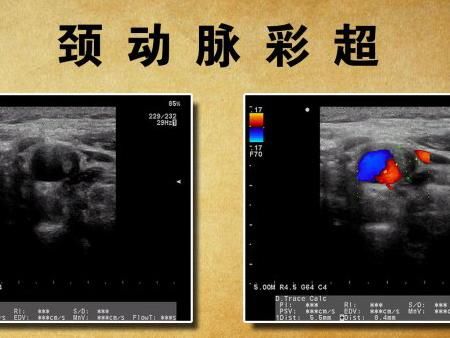

頸動(dòng)脈彩超

??????? 我們?cè)诠?jié)目中介紹過兩種和血管相關(guān)的檢測(cè)方法,經(jīng)顱多普勒和頸動(dòng)脈彩超。有人有點(diǎn)糊涂了,這兩種不都是查血管是不是堵了嗎?有什么不同?經(jīng)顱多普勒觀察腦內(nèi)動(dòng)脈,頸動(dòng)脈彩超觀察頸部動(dòng)脈。這兩種檢查不能互相替代。